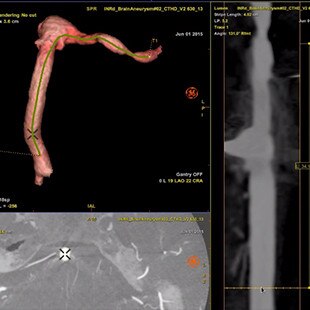

Planifier

Guider

Évaluer